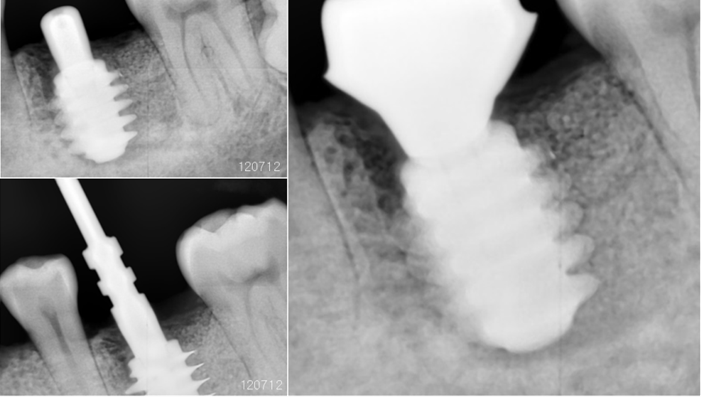

“AnyRidge implant enables fast and stable

osseointegration at this extreme case of bone defect. ”

Clinical case: Bone filling into the bottom of deepest thread at 8.0mm AnyRidge fixture

- Courtesy of Dr. Kwang Bum Park -

Keywords

AnyRidge, Knifethread ,extraction socket, ,initial stability ,Allograft, ,osseointegratio ,Dr. Kwang Bum Park, , Mandibular, Single replacement, AnyRidge, Mega-oss,

Products used

Implant system-AnyRidge, Regeneration-Mega-Oss